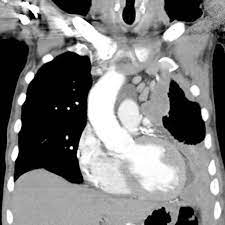

Surgery is a crucial component of mesothelioma treatment, especially in the early stages of the disease when the tumor is localized and has not spread extensively. The main goal of surgery is to remove as much of the cancerous tissue as possible, thus alleviating symptoms and potentially prolonging survival.

In this procedure, the surgeon removes the affected pleura (lining of the lungs) along with any visible tumors. Unlike the more extensive extrapleural pneumonectomy (EPP), P/D preserves the lung, making it a viable option for patients with better lung function.

This aggressive surgical option involves removing the entire lung on the affected side, the nearby pleura, parts of the diaphragm, and the pericardium. EPP is typically reserved for patients with early-stage mesothelioma and good overall health.